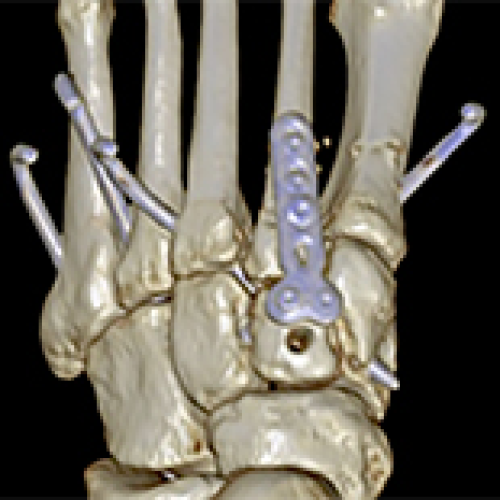

02 Jul 2024 : Clinical Research

Internal Brace Fixation Technique for Lisfranc Injury: A Retrospective Study

Guanglong Zeng, Qingxiang Xie

DOI: 10.12659/MSM.943537

Med Sci Monit 2024; 30:e943537

Guanglong Zeng, Qingxiang Xie, Haobo Huang, Limin Cai, Yongcong Li, Xinyuan Liang, Boyuan Su

5,072